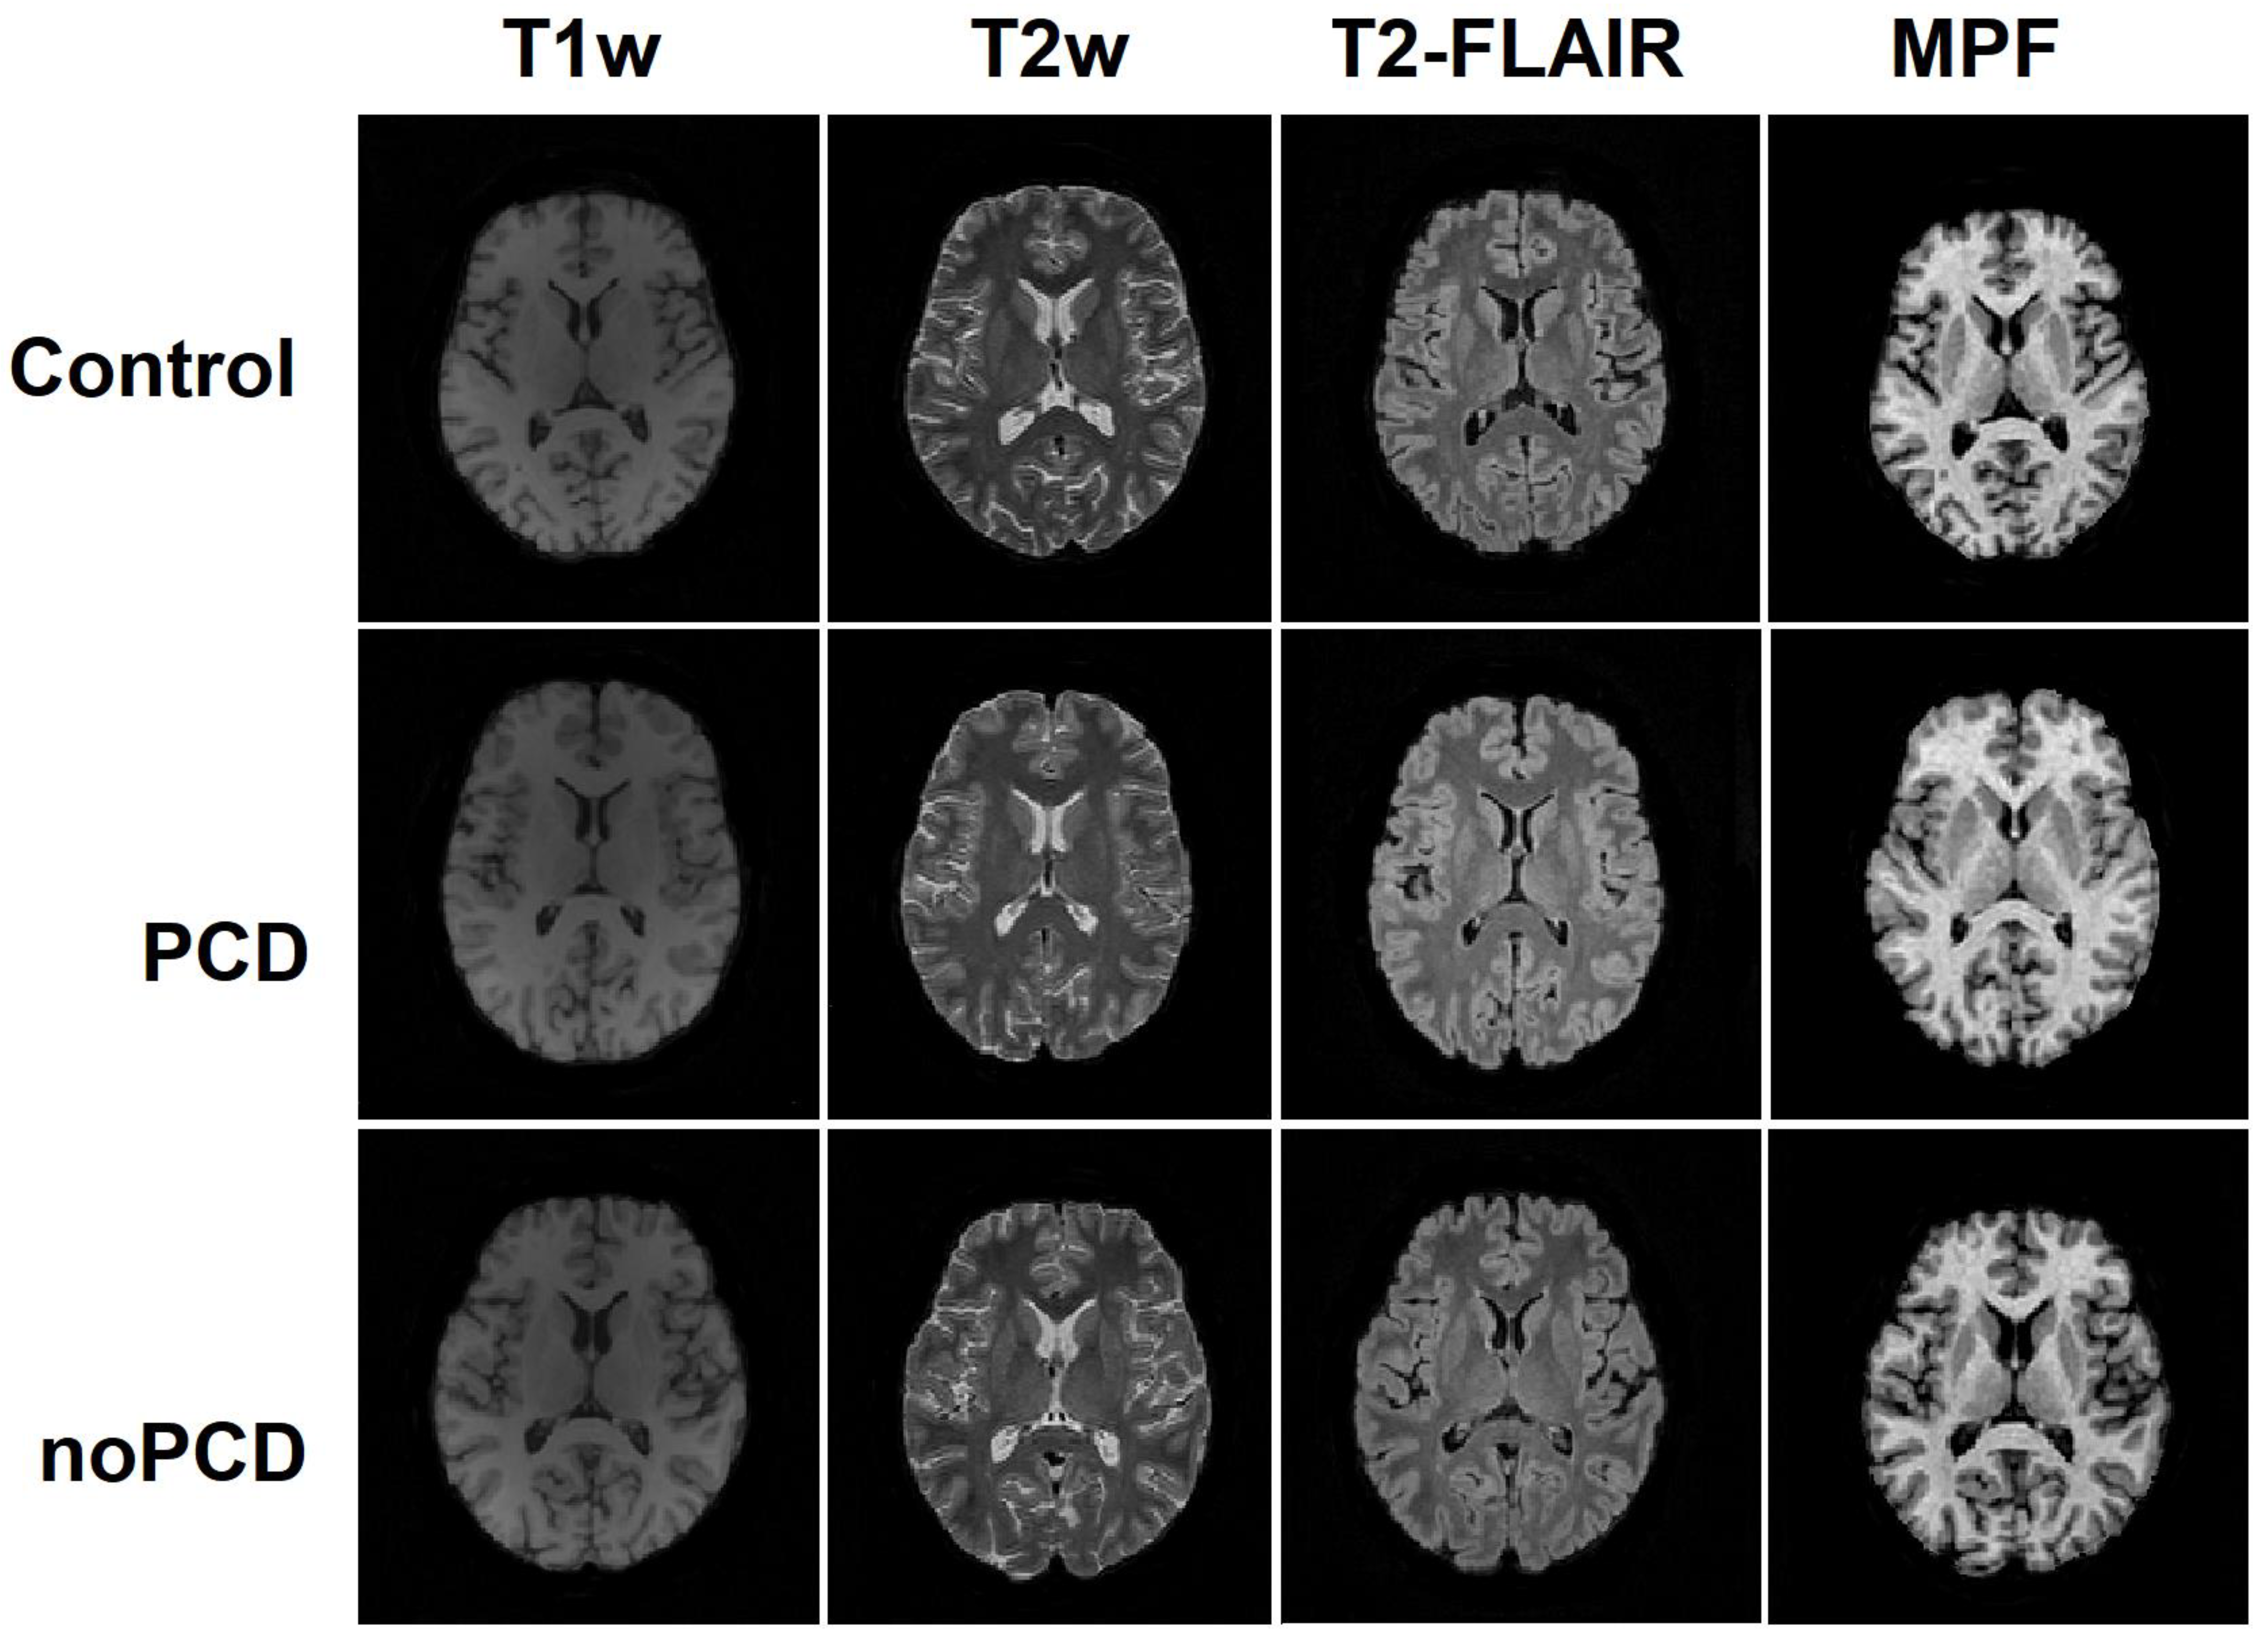

2.3. MRI Data Acquisition

- Magnetization-transfer (MT)-weighted pulse sequence: TR = 20 ms, echo time (TE) = 4.76 ms, flip angle (FA) = 8°, scan time 5 min 40 s;

- T1-weighted pulse sequence: TR = 16 ms, TE = 4.76 ms, FA = 18°, scan time: 4 min 32 s;

- Proton-density (PD)-weighted pulse sequence: TR = 16 ms, TE = 4.76 ms, FA = 3°, scan time: 4 min 32 s.

- The additional imaging sequences included the following:

- 3D Fluid attenuated inversion recovery (FLAIR) pulse sequence: TR = 5000 ms, TE = 390 ms, TI = 1800 ms;

- 3D T1-weighted pulse sequence: TR = 16 ms, TE = 4.76 ms;

- 3D T2-weighted pulse sequence: TR = 3000 ms, TE = 335 ms.